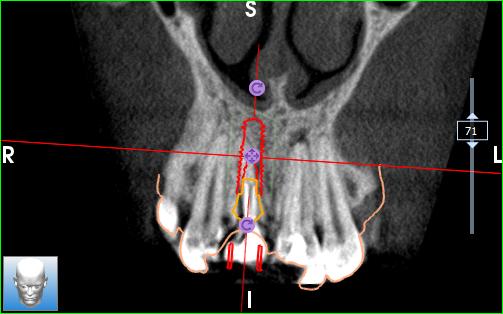

• Bilan 3D ou Tomographie volumique à faisceau conique ou Cone Beam Computed Tomography (Photo 4)

Sur le cone beam réalisé nous retrouvons bien notre lésion latérale au niveau de 11 et notre lésion apicale au niveau de 21. A noter également la fracture palatine du tiers cervical radiculaire.

On note la présence d’une paroi osseuse vestibulaire intacte permettant d’envisager une extraction

atraumatique suivie d’une implantation immédiate, dans de bonnes conditions.